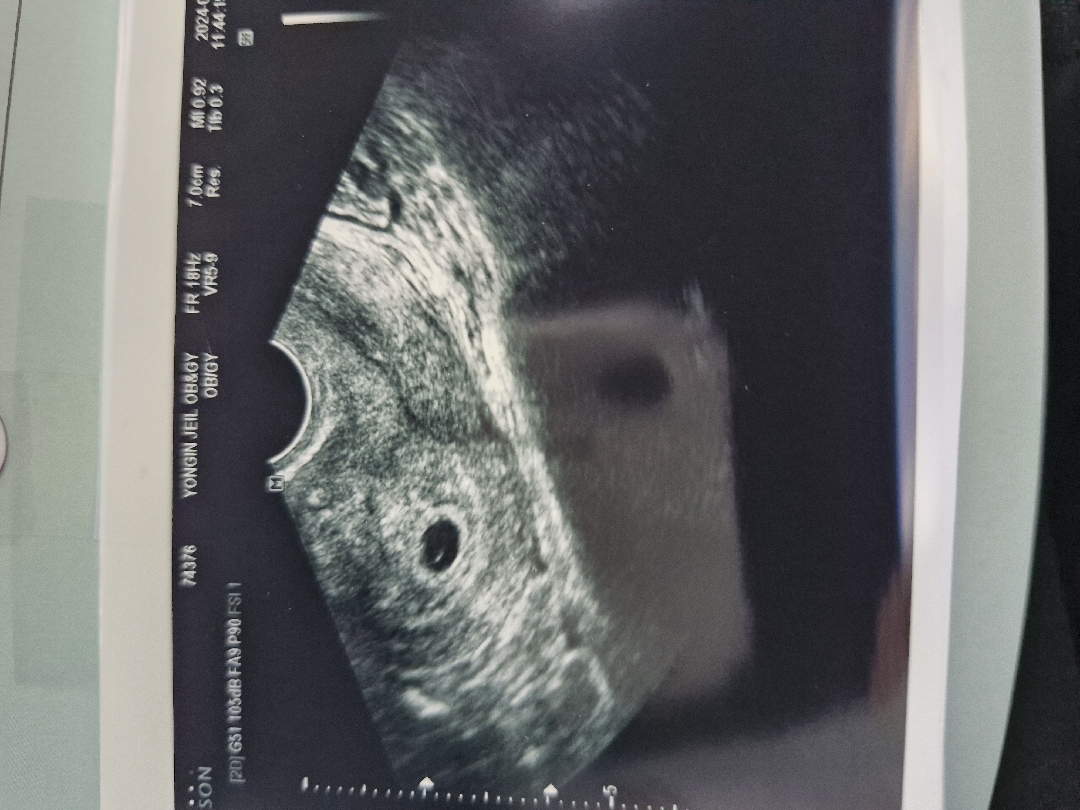

저 5주0일차인데 아기집만봤어요! 담주에 난황보자하셧어요

5주0일 아기집이랑 난황보고왔어요~~

자리는 잘 잡았고 주수보다 2~3일 크다고 하셨는데 난황만보이고 애기는 안보여서요ㅠㅠ원래 그런건가용 담주에 가면 심장소리랑 아기 같이 볼 수 있겠죠?ㅎㅎ